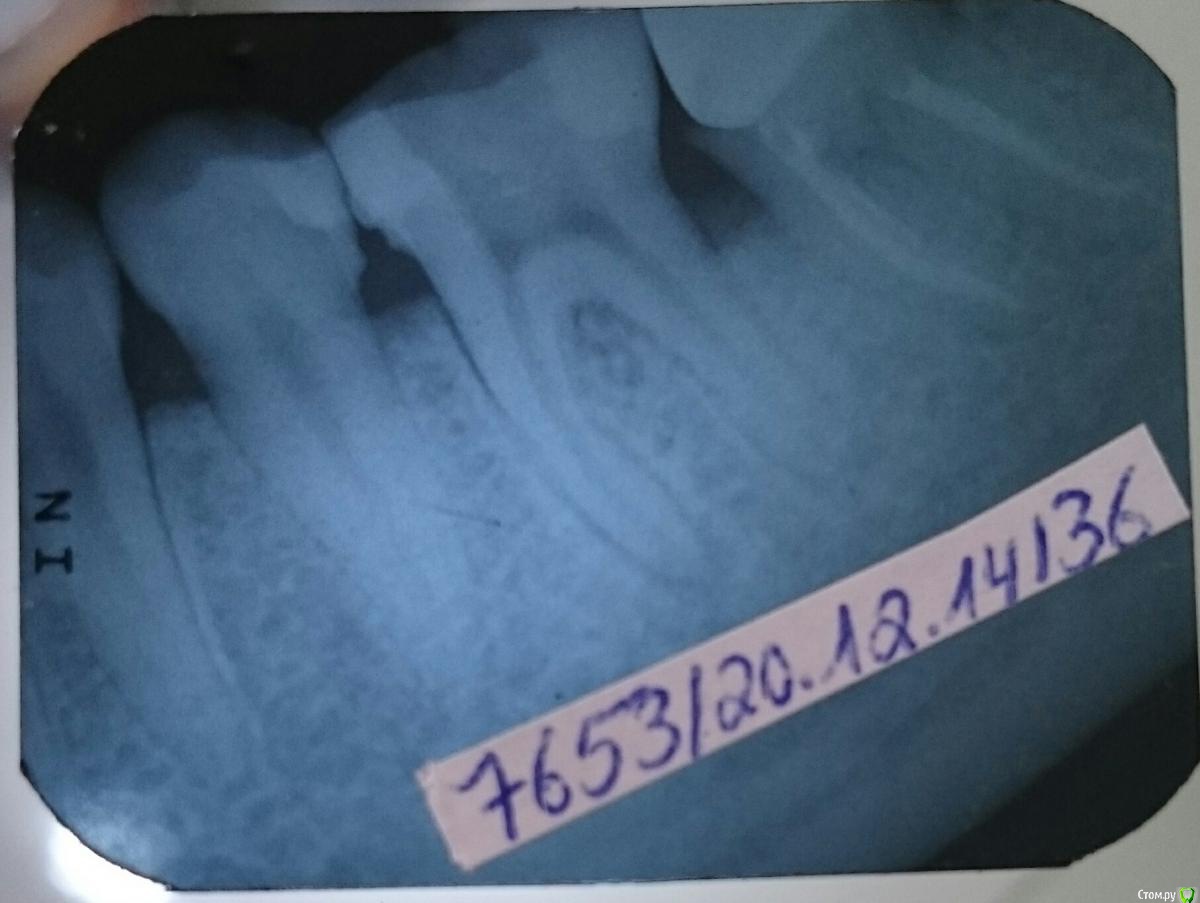

mari100989 Опубликовано 22 декабря, 2014 Поделиться Опубликовано 22 декабря, 2014 (изменено) Здравствуйте! Помогите пожалуйста! Уже не знаю что мне делать.. С 12 на 13 декабря начал болеть зуб. Было такое ощущение, что зуб просто был очень чувствителен к холодному.На следующий день (как на зло был экзамен) выпила ибупрофен 600. Сдала экзамен. Потом боли начались по новой, сразу после экзамена к дежурому врачу. Он ничего не предпринял, сказал что надо, завтра показаться моему врачу. Еще пара таблеток ибу 600. На след. День у моего врача. Спасала холодная вода,успокаивала боль. Доктор сделал снимок, сказал, что корни сгнили или что - то в этом роде. Почистили вытащили нервы,поставили временную пломбы. В этот день все было хорошо, на след. День зуб начал по-тихоньку побаловать. К обеду я не выдержала выпила таблетку которая не помогала, позвонила доктору, сказал выпить еще одну и если не поможет надо приехать. Таблетка помогла,так я прожила еще 2 дня(постоянно принимая таблетки). Боль росла и в Четверг я была опять у врача. Он открыл мне зуб, все еще раз почистил и оставил открытым. Назначил мне антибиотики которые я должна была призменять с воскресенья, чтобы он в среду смог мне запломбировать зуб. Но до среды дело так и не дошло. Почувствовав резкую боль ,позвонила врачу и начала применять первые таблетки антибиотики.уже в 9.30 утра в Пятницу. проснувшись в субботу обнаружила, что моя щека распухла. Поехала к врачу, прочистил мне в очередной раз каналы меня отпустили. Но на следующий день щека стала еще больше. Опять к врачу, там был сделан надрез на десне , чтобы вышел гной.(хотя врач сказал, что десна не такя уж и опухшая и что вся опухоль в основном в щеке.) гной вышел очень слабо. Для такой огромной щеки как у меня это ничего. Еще к тому гной вязкий. Врач сказал, что уже не знает что он может со мной делать.Опухоль на щеке твердая. С вчерашнего дня начала по-тихоньку охлаждать опухоль.Сегодня проснулась опухоль не ушла, хотя и кажется что она стала немного меньше.попробовала не пить ибупрофен. Но стало очень больно. Ибупрофен пью не переставая. Мин. 3 раза в день. Антиьиотики уже 4 й день. 2 раза в день. С сегодняшнего дня хочу применять антибиотики 3 раза в день.. Изменено 22 декабря, 2014 пользователем mari100989 Ссылка на комментарий